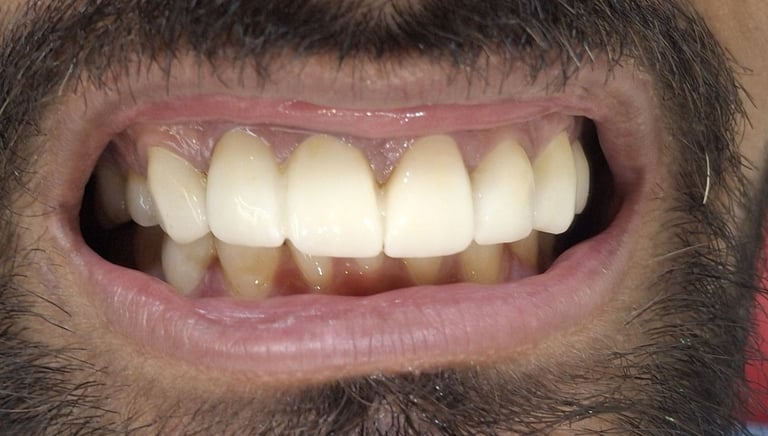

Before

After

All images shown here are real teeth cleaning cases treated at our clinic with patient consent.

Professional teeth cleaning helps remove plaque, tarter, and surface stains that regular at home brushing can not.

At Shree Dental Care, teeth cleaning is performed gently with focus on patient experience, comfort and long term oral health.